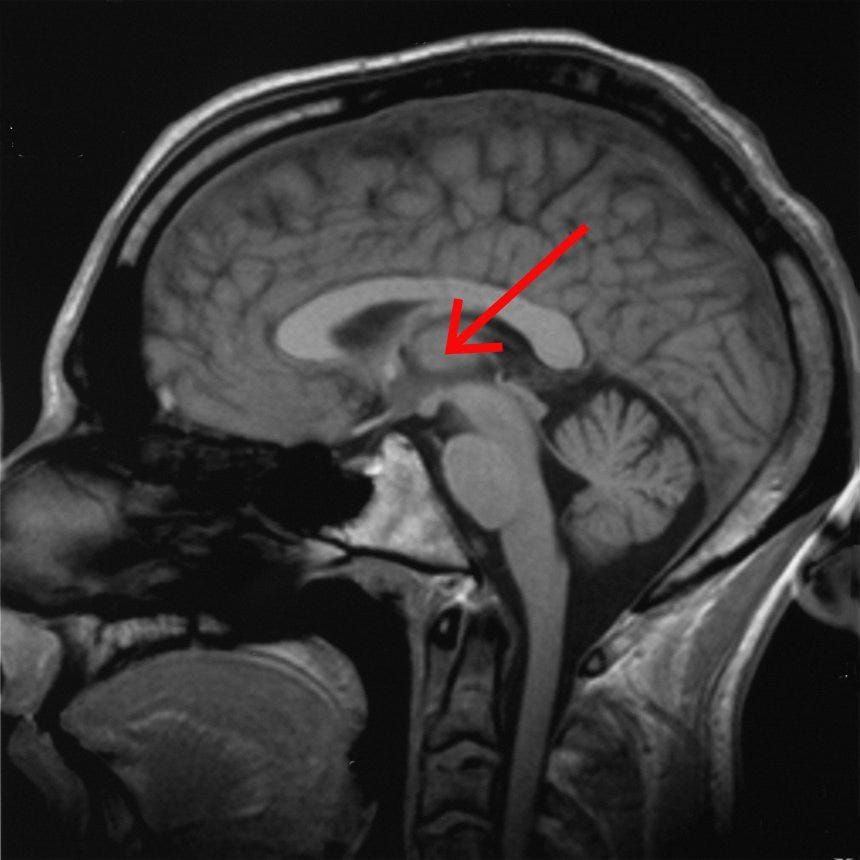

At a first approximation, it’s the thalamus, stupid.

During less-conscious states, the thalamus is less active, more inclined to slow synchronized firing than fast desynchronized firing, and less “functionally connected to” (i.e. activity correlates less well with) other brain regions, particularly in the cortex.

Interestingly, my last (imperfect) candidate for a brain region critical for conscious sensory perception was a particular nucleus in the thalamus.

While lesions in many places can cause disorders of consciousness, the thalamus is a common lesion site, as well as a network of fronto-parietal cortex sites known as the default mode network (which is typically active during self-related thought processes like mind-wandering and autobiographical memory.)

But we do have a very clear and consistent signal that virtually all unconscious states involve alterations in the thalamus, which is intriguing because the thalamus is also the connecting hub that integrates between different sensory perceptions and the cortical regions that process them.